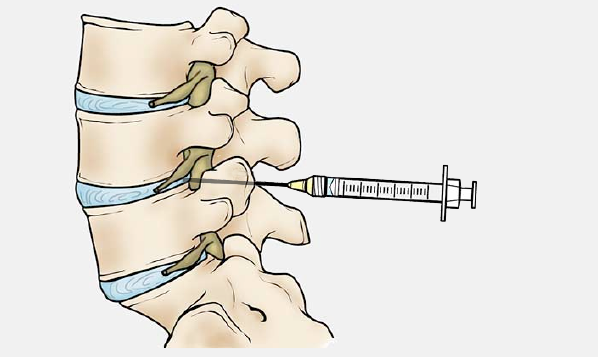

The combination of stem cells and tissue specific lymphocytes are injected into the affected intervertebral discs. The procedure is performed in a CT scanner or under fluoroscopic guidance.Most patients can quickly return to their usual routines with minimal interruption. A slight swelling or mild discomfort at the injection site may occur but typically resolve within a few days, allowing for a smooth recovery.